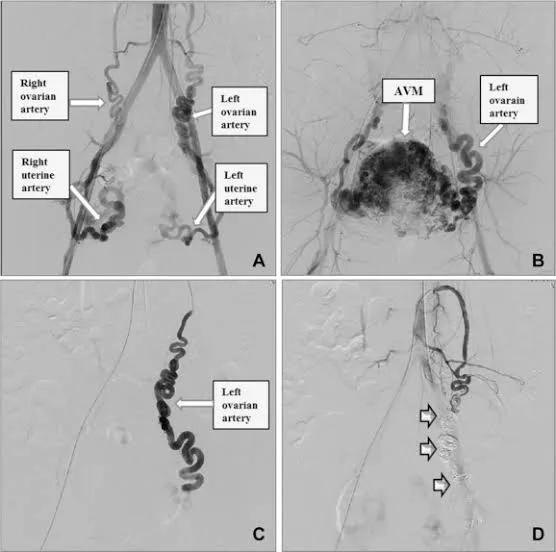

Uterine Arteriovenous Malformation (Uterine AV Malformation)

Uterine Arteriovenous Malformation (Uterine AVM) can be considered as a situation in which arteries as well as veins in the uterine region have a malformation or abnormal connection. The most important point about this health issue is that this malformation can lead to sudden uterine bleeding. The best treatment form in this case can be Uterine Artery Embolization.

Step 4: Embolization (Reduction of Blood Flow) Embolic particles are injected through the catheter to decrease blood flow to the selected branches of the uterine artery. This is the definitive step. For fibroids, reduced blood flow causes fibroids to shrink gradually. Reducing blood flow will assist in stopping the bleeding in cases of postpartum hemorrhage.